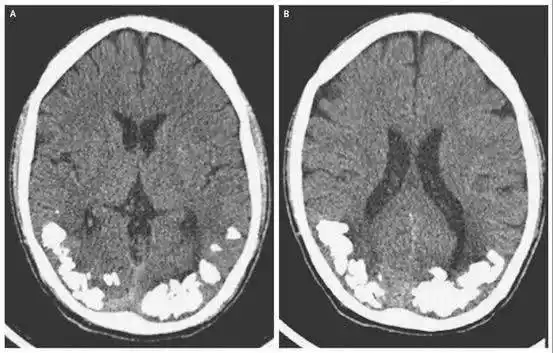

科学普及大脑也会得结石浅谈脑结石

脑出血图像04做ct对人体会有危害吗?